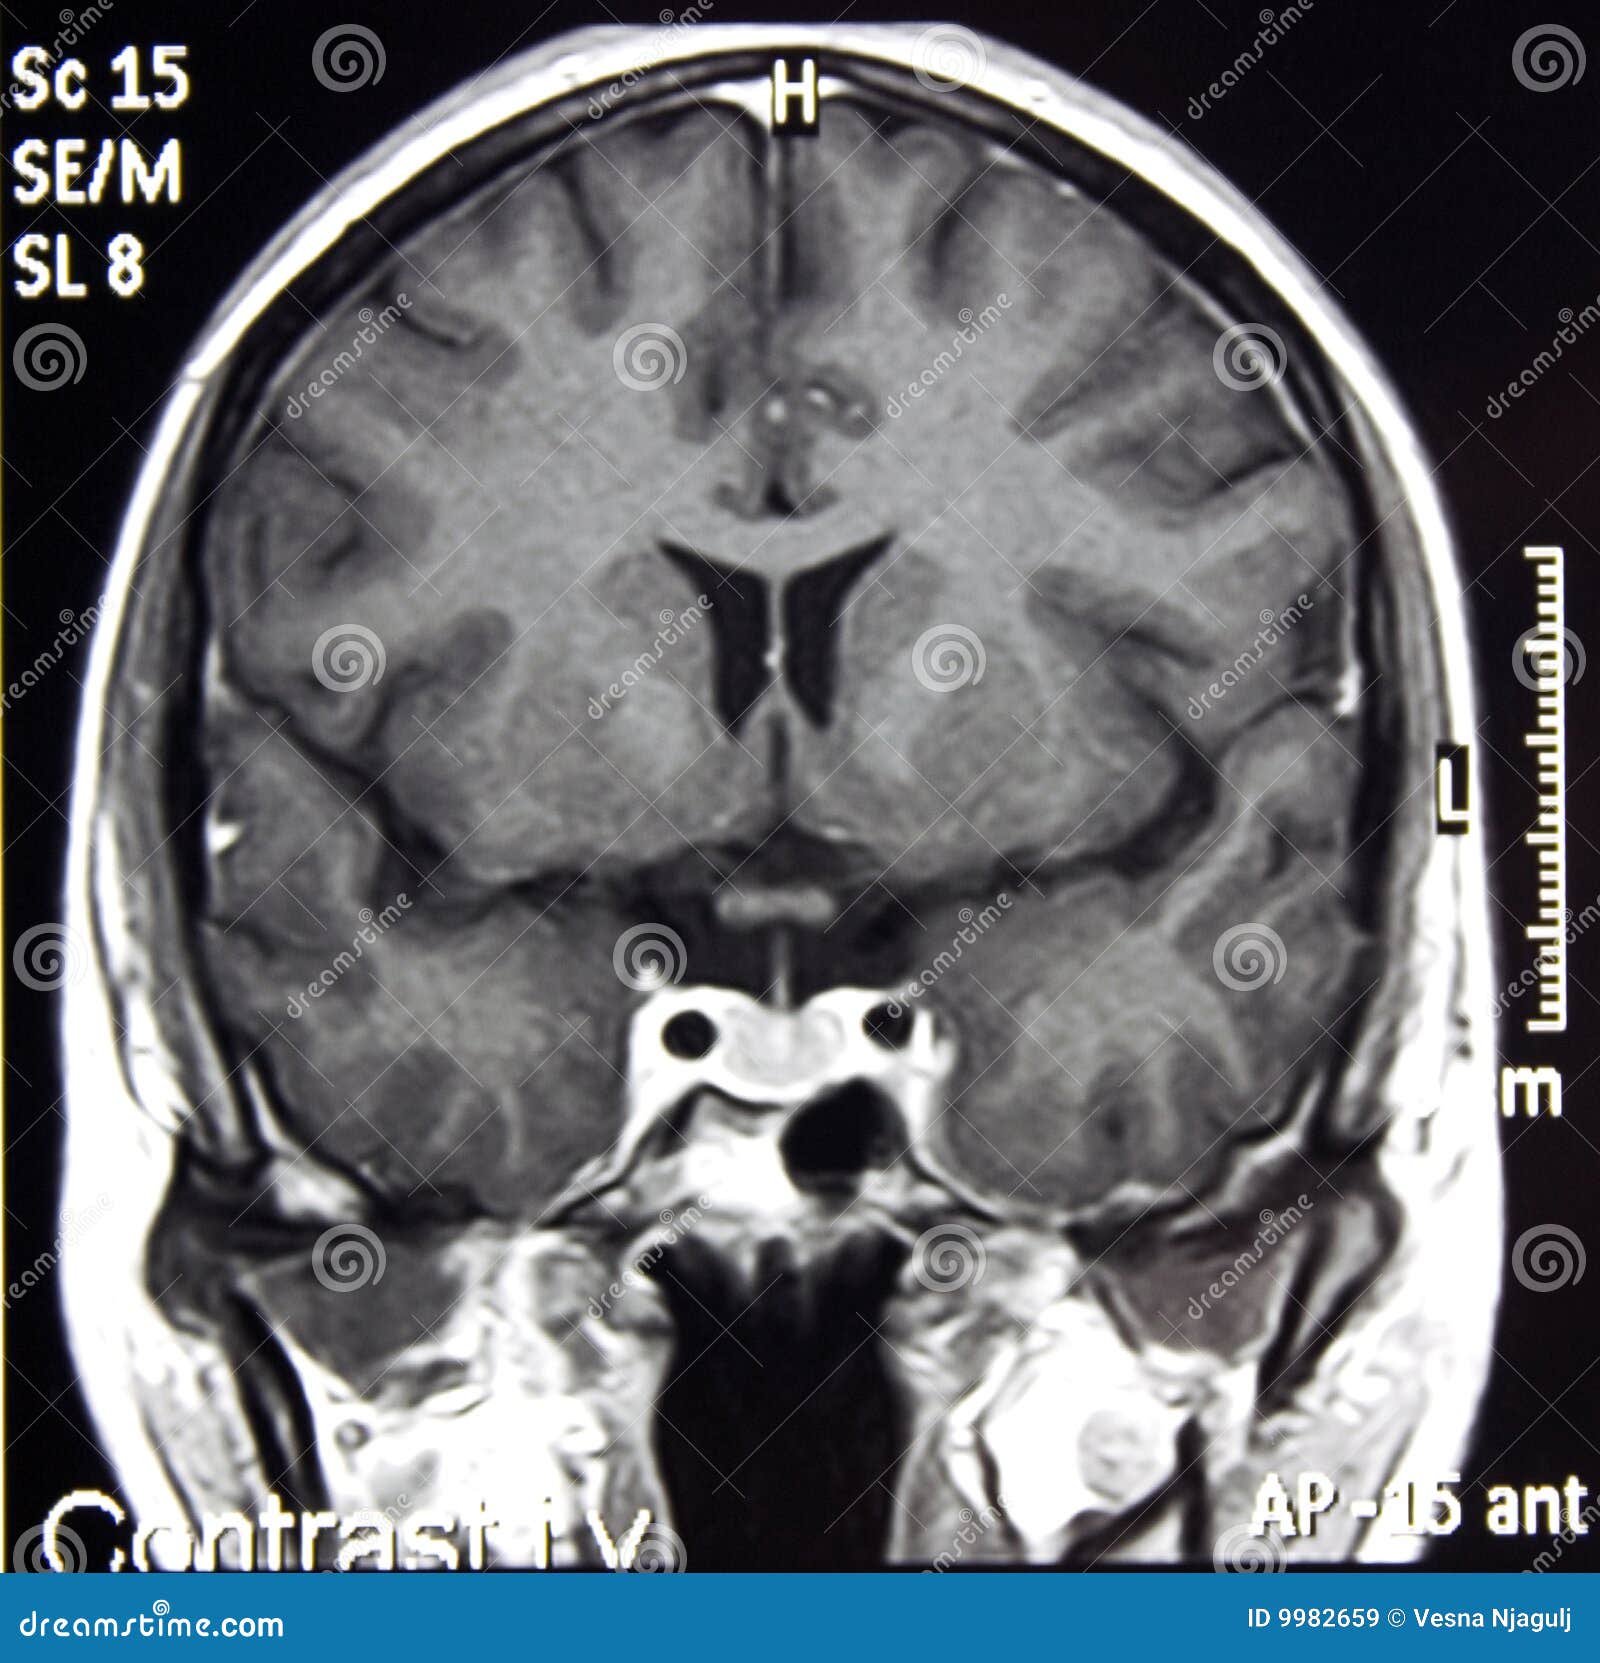

Lista muestra hermosas imágenes de resonancia magnética cerebral normal y anormal dinosenglish.edu.vn para que puedas explorar más en detalle.

resonancia magnética cerebral normal y anormal Pin en NEUROCIENCIAS resonancia magnética de cerebro Resonancia magnética (RM) de cerebro, corte axial ponderado en T2: la … VIDEO Nueva mancha en la Resonancia

Engineer Team : RESONANCIA MAGNETICA Magnetic Resonance Imaging – Clinical Images Hallazgos por resonancia magnética cerebral de nuestro paciente. M, 21 … Imágenes por resonancia magnética anormales como predictoras de mal … Imágenes por resonancia magnética anormales como predictoras de mal … Lesiones en resonancia magnética (RM) del encéfalo y la médula espinal … Pin en Resonancia Magnética del Encéfalo A) Resonancia magnética cerebral (RMC) mostrando infartos en … Caso 1: Edema cerebral visualizado mediante RM. (A) Secuencia T1 plano … Rascacielos dormir pasta tac y resonancia diferencias retrasar … Pin on Apuntes de Enfermería y T.C.A.E Resonancia magnética cerebral secuencia T2, que muestra lesión … Meningitis aguda en la enfermedad de Behçet | Reumatología Clínica Resonancia magnética coronal normal del cerebro Fotografía de stock – Alamy Imágenes de resonancia magnética, la imagen de la cabeza en diferentes … Resonancia magnética cerebral A) protocolo T1 sagital (Caso 1). Se … Resonancia magnética cerebral. Secuencia T1 corte sagital. Atrofia … Resonancia magnética de cerebro, cortes axiales, secuencias T2. Señal … Resonancia magnética de cráneo. A y B) Cortes axiales FLAIR … Resonancia magnética (RM) de cerebro, corte axial ponderado en T2: la … RM cerebral: Interpretación paso a paso | Kenhub Resonancia magnética de cerebro, cortes axiales, secuencias T2. Señal … De Resonancia Magnética De Cerebro Foto de archivo – Imagen de arteria … Top 107+ Imagenes de resonancia cerebral normal – Destinomexico.mx -Imagen por resonancia magnética del cerebro. a) Cortes sagital y axial … resonanCia magnétiCa Cerebral donde se observa hiperintensidad a nivel … MRI (Imagen de resonancia magnética) – Tomografía computarizada de la … Meningioma – NCI Imágenes por resonancia magnética coloreadas del cerebro sano del … Resonancia magnética cerebral en secuencia FLAIR, que muestra lesiones … Contraste resonancia magnetica cerebral – senturinthegreen Relación de los espacios de Virchow-Robin con la enfermedad de … Gliomatosis cerebral – Instituto Nacional del Cáncer Pin en Neurology. Recomendaciones para la utilización e interpretación de los estudios de … Fotografía De La Proyección De Imagen De Resonancia Magnética Del … atmósfera Dirigir Cumplir anatomia resonancia magnetica Desarrollar … Pin en #MEDICINA,#SALUD Resonancia magnética de la nasofaringe De Resonancia Magnética De Cerebro Foto de archivo – Imagen de polilla … Atrofia cortical global de predominio parietal en la Resonancia … Resonancia magnética cerebral | Download Scientific Diagram Neuroblog: Resonancia magnética cerebral en la trombosis crónica de … De Resonancia Magnética De Cerebro Imagen de archivo – Imagen de … ¿Cuáles son los riesgos de la resonancia magnética? – Integra Salud … Resonancia magnética cerebral al decimocuarto día de ingreso: área … Resonancia magnética. Corte axial mostrando área infartada en el … Resonancia magnética cerebral del paciente AV evidenciando lesiones en … -Ressonância magnética de encéfalo mostrando múltiplas imagens … Resonancia magnética cerebral secuencia FLAIR (Fluid Attenuated … Resonancia magnética cerebral con protocolo de epilepsia, en sección … Resonancia magnética cerebral en corte sagital. Se observa una evidente … Resonancia magnética craneal en la que se evidencian lesiones … Logran visualizar el cerebro a detalle más completo tras una resonancia … Así decide el cerebro la severidad de un castigo De Resonancia Magnética De Cerebro, Imagen de archivo – Imagen de … A) Resonancia magnética cerebral; Secuencia Tof: oclusión de arteria … Un estudio asocia la ansiedad con la aparición rápida del Alzheimer IMÁGENES DE 18 F-PR04.MZ PET FUSIONADA CON RESONANCIA MAGNÉTICA … Imágenes por resonancia magnética anormales como predictoras de mal … Tumores de la región pineal – Instituto Nacional del Cáncer Epilepsia: una historia de voces y fantasmas | Neurología Contribución de las imágenes de resonancia magnética por tensor de … Resonancia magnética secuencia T2 plano coronal de quiste epidermoide … Resonancia Magnética Cerebral del paciente: a. Aumento de… | Download … Resonancia magnética cerebral 2022 Síndrome de hemiconvulsión-hemiplejía-epilepsia. Seguimiento de un caso … Enfoque Radiologico: La resonancia magnética permite detectar lesiones … Resonancia magnética craneal T1 con contraste que muestra angiomatosis … guidewiz – Blog Resonancia magnética cerebral, secuencia SWI. Ribete hipointenso en la … resonAnCiA mAgnétiCA de ColumnA Con gAdolinio. Corte sAgitAl en t1 de … SEMANA 12: FUNDAMENTOS DE RESONANCIA MAGNÉTICA NUCLEAR. INDICACIONES Y … DIAGNÓSTICO DE ESCLEROSIS MÚLTIP Magnetic resonance imaging of the brain – Alchetron, the free social … Resonancia magnética de órbitas | Instituto Radiológico Dr. E Castillo Alteración de la marcha en un paciente post-trasplante hepático Resonancia magnética cerebral de un paciente sano (Ay B) y paciente que … Utilidad de la resonancia magnética craneal para el diagnóstico de la … Resonancia Magnética Del Cerebro El Tumor Cerebral Foto de stock y más … De Resonancia Magnética De Cerebro Imagen de archivo – Imagen de … ABDALLA RADIOLOGIA: NEURINOMA ACUSTICO Atrofia cortical global de predominio parietal en la Resonancia … Resonancia Magnética : Producción de la imagen MRI Brain Scan — Stock Photo © Bunyos30 #18724051 Mri (imagen de resonancia magnética) Monitor con imagen de captura de … Tomografía computarizada vs resonancia magnética: diferencia y … Tumores Cerebrales – Unidad de Neurocirugía RGS Resonancia magnética de la columna, sección sagital. Observe los discos … La resonancia magnética, una técnica imprescindible en el diagnóstico … Perfusión Cerebral por Resonancia Magnética | ¿Qué es? ¿Necesita Contraste? Resonancia Magnética Cerebro A: resonancia magnética, T2 coronal preoperatoria; se observa lesión en … Resonancia magnética cerebral — Foto de stock © Bunyos30 #27340623 La resonancia magnética se perfila como detector de mentiras | Futuro … Resonancia magnética cerebral en T1 con gadolinio, cortes axial (a … MRI brain : show brain tumor at right parietal lobe of cerebrum — Stock … NEUROIMÁGENES EN ENFERMEDAD DE PARKINSON: ROL DE LA RESONANCIA …